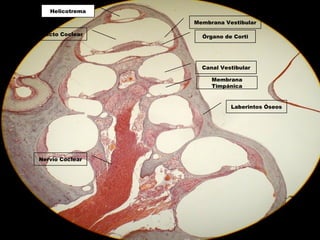

Laberintos Óseos

Órgano de Corti

Membrana Vestibular

Helicotrema

Nervio Coclear

Canal Vestibular

Membrana

Timpánica

Conducto Coclear